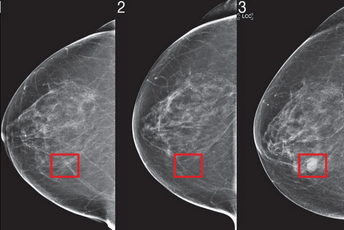

MIT je koristio vještačku inteligenciju kako bi predvidio razvoj raka dojke. Na fotografijama modela koje proizvodi moguće je vidjeti dio tkiva koji je identifikovan kao područje visokog rizika koji je četiri godine kasnije prerastao u karcinom.

"Mnogo je na fotografiji abnormalnosti koje vidite, ali to su zapravo promjene koje nisu karcinom. Ne možemo sve zvati karcinomom jer bi onda svako ko ide na mamografiju morao ići i na biopsiju. To nije baš praktično. Ono što radi MIT je identifikovanje područja visokog rizika prije no što u njima razvije rak dojke. Ono što ljudsko biće može, ali mašine ne, jeste naručivanje dodatnih testova kao što su mamografi sa kontrastom ili magnetna rezonanca", objasnio je Norton, prenosi Klix.ba.

Prije dvije godine, tim naučnika iz Laboratorije za kompjuterske nauke i vještačku inteligenciju MIT-a i klinike Jameel demonstrirao je sistem dubokog učenja za predviđanje rizika od raka koristeći samo pacijentov mamograf.

U tu svrhu, oni su svoj "Mirai" algoritam prilagodili kako bi obuhvatili jedinstvene zahtjeve modelovanja rizika.

Mirai modelira pacijentove faktore rizik u više budućih vremenskih tačaka i opcionalno može koristiti i kliničke faktore rizika kao što su starost ili porodična anamneza, ukoliko su dostupni.